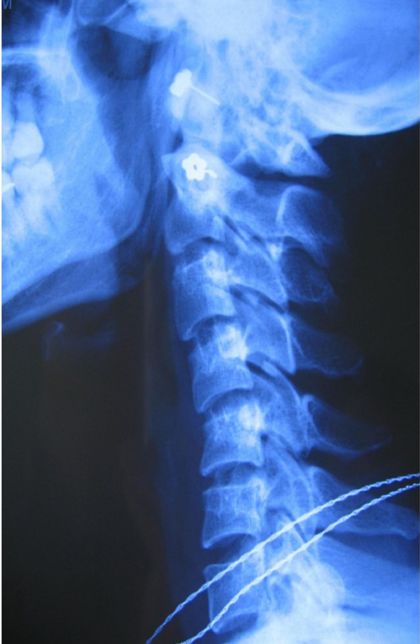

1.颈型颈椎病

又称韧带关节囊型颈椎病,急性发作时常被俗称"落枕"。该型颈椎病多因睡眠时枕头高度不合适或睡姿不当,颈椎转动超过自身的可动度,或由于颈椎较长时间弯曲,一部分椎间盘组织逐渐移向伸侧,刺激神经根,而引起疼痛。"落枕"也不排除非颈椎因素。如颈部肌肉受寒出现风湿性肌炎、项背肌劳损或颈部突然扭转等,亦可导致"落枕"样症状。

颈型颈椎病症状,以颈部僵硬、痛、胀及不适感为主,常在清晨醒后出现或起床时发觉抬头困难,患者常诉说头颈不知放在何种位置为好。约半数以病人颈部活动受限或强迫体位,个别病人上肢可有短暂的感觉异常。活动时疼痛加剧,休息可以缓解。

此型颈椎病病程较长,可持续数月甚至数年,且常反复发作或时轻时重。慢性病程患者主诉头部转动时发生奇异的响声。发作时,患者头部偏向患侧,以缓解疼痛及不适。